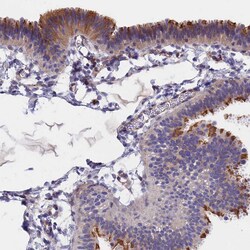

Immunogen sequence: KRTAVRLGDP HFYQDSLWLR KEFMQVRR Highest antigen sequence identity to the following orthologs: Mouse - 96%, Rat - 96%.

| Antigen | TMEM138 |

| Anwendungen | Immunohistochemistry (Paraffin), Western Blot |

| Gen | TMEM138 |

| Gen-Alias | HSPC196; HSPC198; JBTS16; TMEM138; Transmembrane protein 138 |